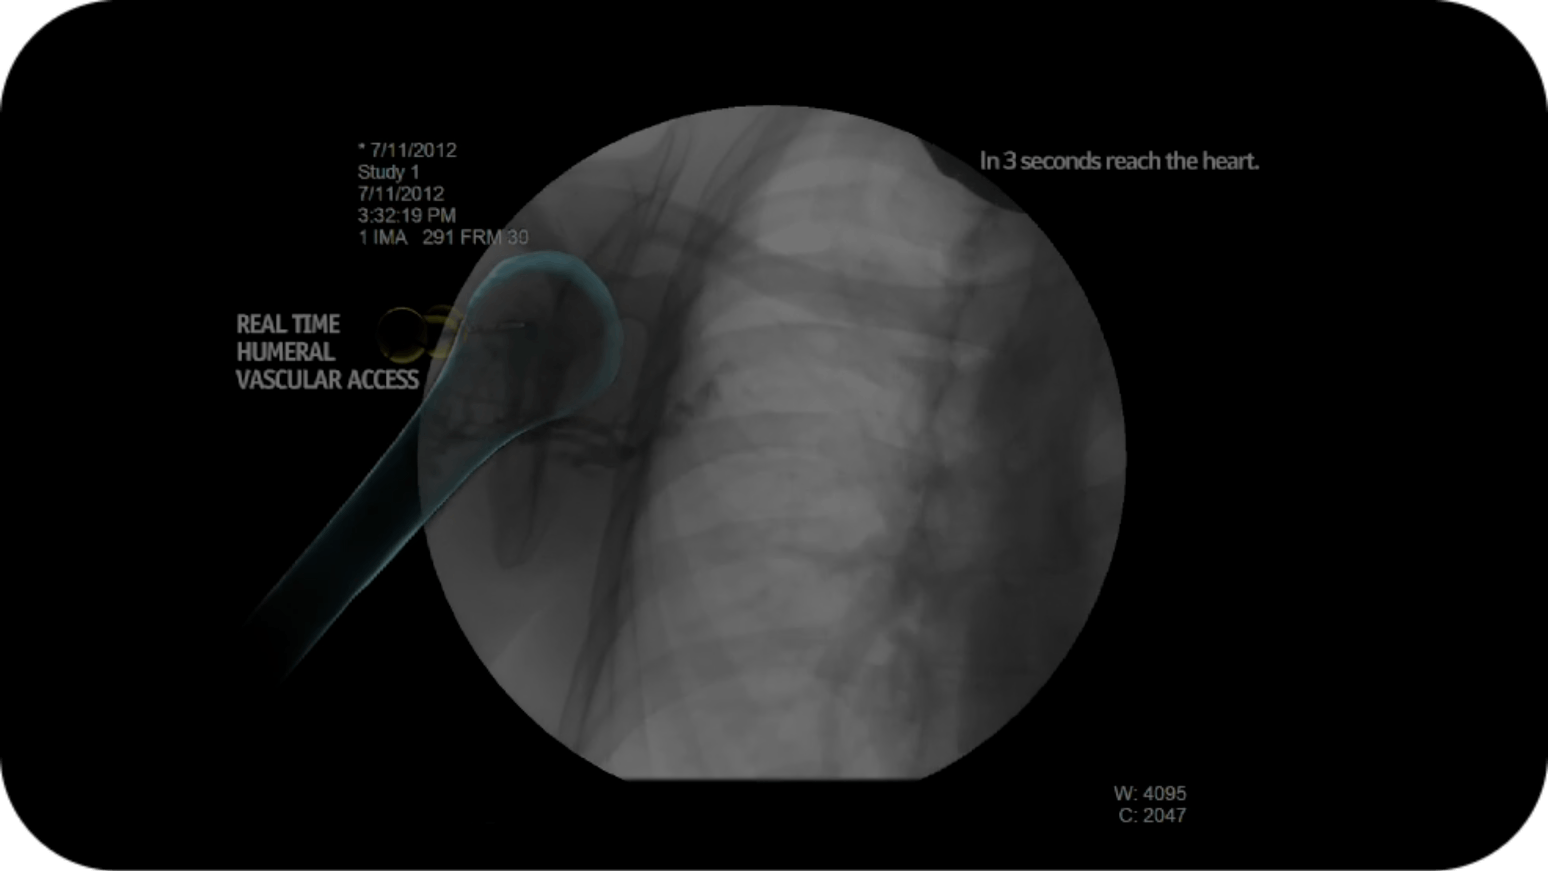

Arrow EZ-IOシステムは、一刻を争う際に必要な性能を発揮します。Arrow™ EZ-IO™システムは15年を超える臨床研究と

実証された7成功に裏打ちされており、血管確保が困難な患者さん(DVA)に対して、すばやく8効果的な9解決策となります。